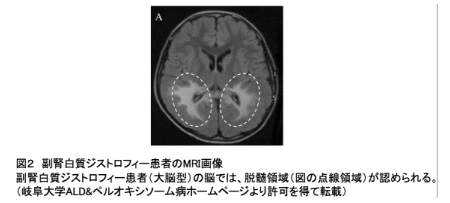

極長鎖脂肪酸は一部の細胞で利用される一方、大部分の細胞では、極長鎖脂肪酸を運ぶ特殊な輸送タンパク質の働きによって分解されます。我が国の難病に指定される副腎白質ジストロフィー(指定難病20)は、この輸送タンパク質の機能が遺伝的に不全であるために生じます。副腎白質ジストロフィーは、脳の中の炎症反応を伴う進行性の脱髄症状※6(図2)や、副腎機能の不全を特徴とする疾患です。

【画像:https://kyodonewsprwire.jp/img/202601293228-O5-WTI8b5Gr】